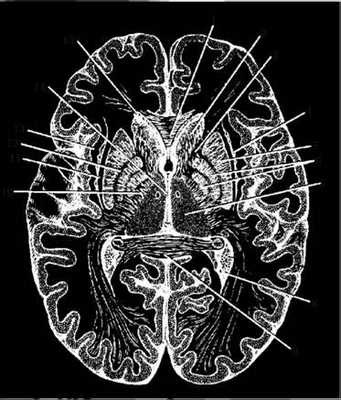

Рис. 3.27. Горизонтальный разрез головного мозга:

1 - лобные щипцы; 2 - головка хвостатого ядра; 3 - передняя ножка внутренней капсулы; 4 - ограда; 5 - скорлупа; 6 - бледный шар; 7 - таламус; 8 - задний рог бокового желудочка; 9 - затылочные щипцы; 10 - задняя ножка внутренней капсулы; 11 - наружная капсула; 12 - мозговая полоска; 13 - самая наружная капсула; 14 - третий желудочек; 15 - передний рог бокового желудочка

Рис. 3.28. Расположение проводящих путей во внутренней капсуле:

1 - корково-стриарный путь; 2 - чечевицеобразное ядро; - лобно-мостовой путь; 4 - корково-ядерный путь; 5 - корково-спинномозговой путь; 6 - таламо-корковый путь; 7 - затылочно-височно-мостовой путь; 8 - слуховая лучистость; 9 - зрительная лучистость; 10 - таламус; 11 - головка хвостатого ядра

Колено внутренней капсулы занимает корково-ядерный путь. Заднюю ножку образуют корково-спинномозговой путь, таламо-корковый путь, затылочно-височно-мостовой путь, затем располагаются волокна, происходящие из ядра медиального коленчатого тела - слуховая лучистость (коленчато-височный путь) и, наконец, волокна из ядра латерального коленчатого тела - зрительная лучистость (коленчато-шпорный путь).